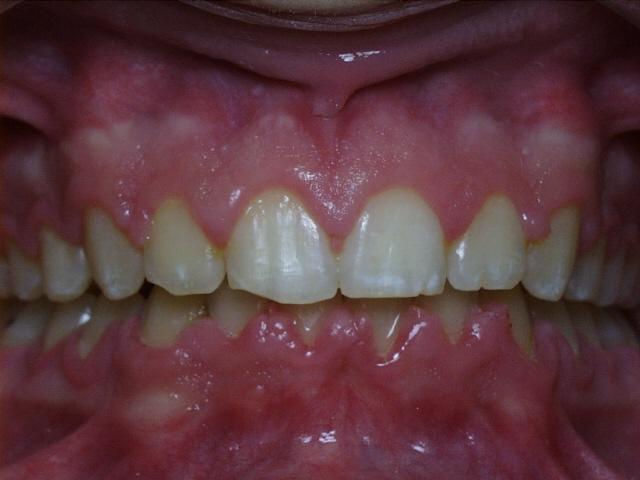

Severe crowding with a crossbite of the front teeth.  Treatment time was 18 months.  This case required the extraction of four permanent teeth.  The molars were class 1 (upper and lower molars met properly at start of treatment).  This patient's teeth are discolored in the final photo because of poor oral hygiene while wearing braces.

Before  rpao1.jpg (28965 bytes)     rpao3.jpg (27357 bytes)  After